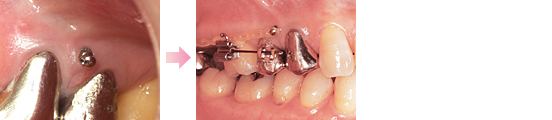

このままの状態では保存が難しい、または無理に治療しても予後に影響のでるような歯があります。

現在の詳しい状態をレントゲンやスライドお写真にて説明して、了解が得られた場合以下のような治療を行う場合があります。

など

| 施術料金 | 1本 | 66,000円~ (税込) |

| ホワイトクラスプ加算 | 22,000円~ (税込) |

| 月額チェック料金 | 一ヶ月 | 5,500円 (税込) |

症例にもよりますが3~6ヶ月くらいが治療の目安になります。

補綴物は別途料金が発生いたしますので、あらかじめご了承ください。